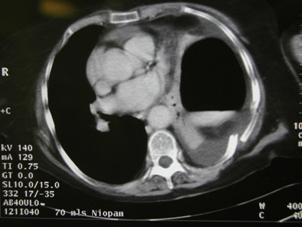

Aspect radiologic Imagine CT

Pneumotorace sufocant bilateral Pneumotorace sufocant stang

Imagine

CT Imagine CT